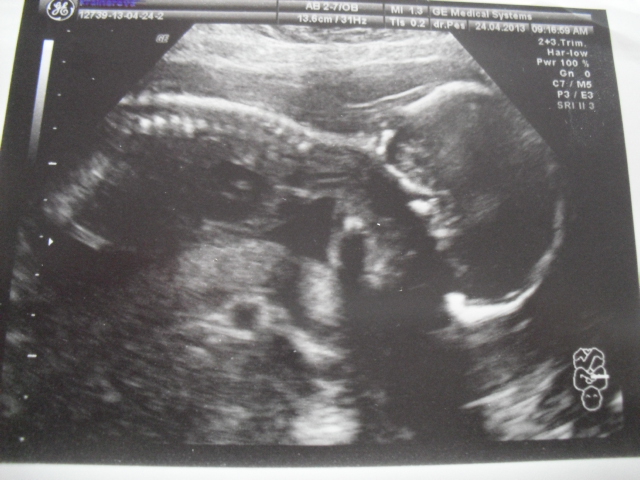

Tady Vám přikládám nějaké fotečky z UTZ, sice nejsou úplně nová, ale alespoň nějaké! Ať vidíte, jak nám maličký roste!

Jinak krany fotečky,je vidět jak hezky roste